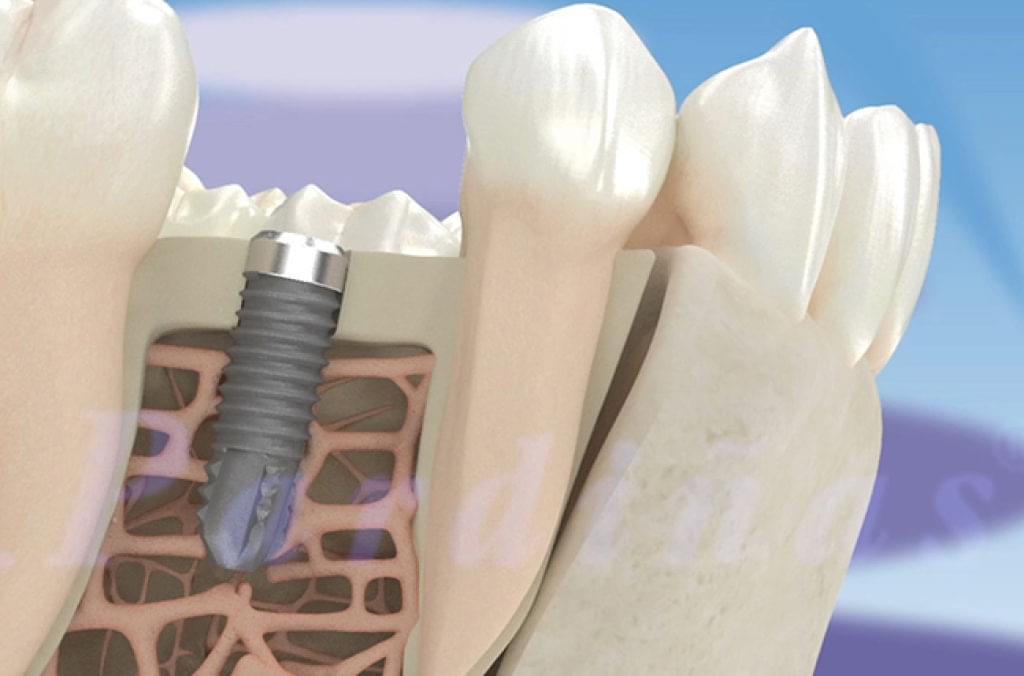

Los implantes de dientes son la mejor opción para reemplazar dientes caídos. La implantología dental conlleva la incorporación de pernos metálicos de titanio que se introducen mediante una cirugía menor para asegurar que se fijen completamente en el hueso maxilar que se encuentra debajo de las encías.

Los implantes dentales de titanio biocompatible quedarán pegados al hueso y se unirán poco a poco mediante el proceso de osteointegración y llevará entre 3 y 4 meses de tiempo.

Los implantes dentales están frabricados con titanio, un material altamente biocompatible con nuestros tejidos y huesos.